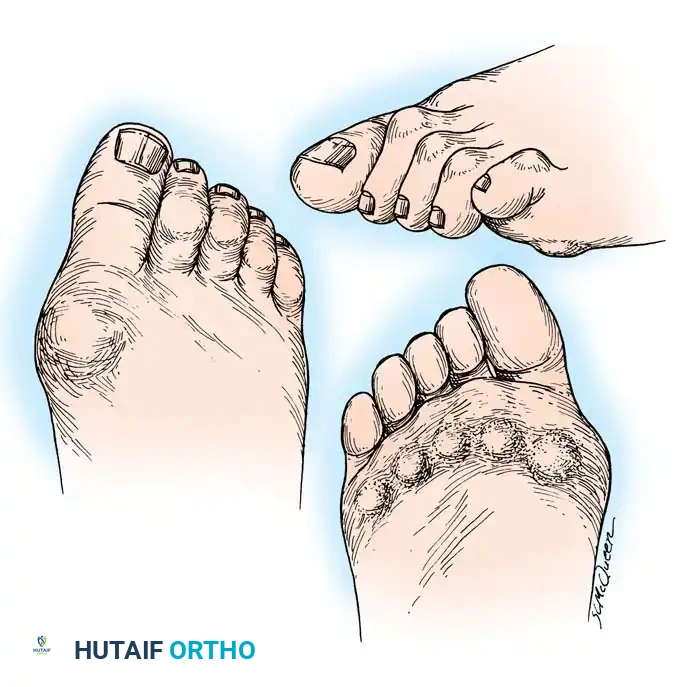

Fig. 81-1 Rheumatoid foot. Note the multiple severe deformities characteristic of rheumatoid arthritis of the forefoot, including advanced hallux valgus, subluxed and dislocated lesser metatarsophalangeal joints, claw toes, hammer toes, and prominent bursal formation.

The hyperextension and eventual dislocation of the MTP joints yield several clinically significant and highly symptomatic deformities:

- Distal Migration of the Plantar Fat Pad: As the proximal phalanx dislocates dorsally, it drags the plantar aponeurosis and the protective plantar fat pad distally.

- Intractable Plantar Keratoses (IPKs): The metatarsal heads are left completely uncovered and prominent against the plantar skin, leading to painful callosities and a high risk of skin ulceration.

- Digital Contractures: Fixed flexion contractures of the PIP and DIP joints (claw toes) and the interphalangeal joint of the hallux develop.

- Dorsal Prominences: Painful hard corns form over the dorsum of the PIP joints, and end corns develop at the nail-pulp junction due to abnormal weight-bearing on the toe tips.

Fig. 81-4 Multiple deformities of rheumatoid arthritis. Note the prominent bursa directly over the medial eminence and the severe dorsal posturing of the lesser digits.

Epidemiological data strongly supports the prevalence of these deformities. Vidigal et al. evaluated 104 patients with RA and noted that 77% exhibited lesser MTP joint subluxation, with 30% developing pressure lesions secondary to hammer toes. Furthermore, hallux valgus deformity was present in 70% of these patients, often accompanied by a varus deformity of the fifth digit.